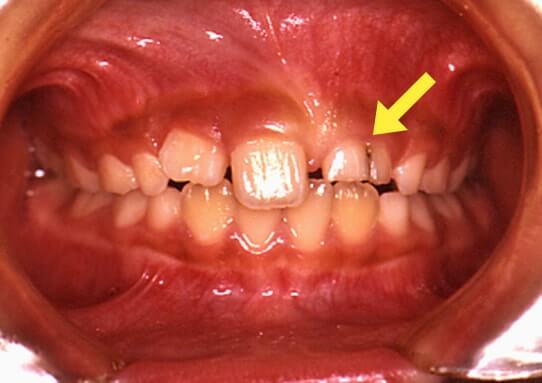

萌出異常(乳歯の裏から歯が生えてきた)